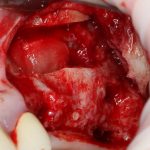

Подготовка костного ложа и фиксация аутотрансплантата

Возвращаемся к основной операционной области. Еще раз посмотрим на альвеолярный гребень, поофигеваем от его ширины и моих грандиозных планов:

Я зафиксировал костный блок практически без адаптации на несколько винтов. Обрати внимание, что винты находятся в зоне, где не планируется установка имплантатов. Фиксация должна быть надежной, поскольку мне еще предстояла подготовка лунок для имплантатов. Трех винтов для этого вполне достаточно.

Дальнейшая адаптация костного блока свелась к сглаживанию острых краев. После чего я приступил к подготовке лунок и установке имплантатов.